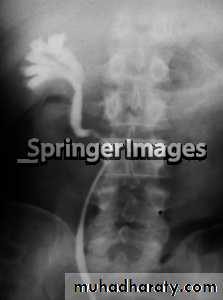

Ureterocele :

Congenital cystic dilatation of lower end of ureter ( intra-mural part) due to pin-hole meatus . May be simple or ectopic .

IVU :

- There is rounded or elliptical dilatation of lower end of ureter with thin lineal filling defect around it , resembling (cobra head appearance),

- Proximal dilatation of rest of ureter .

- In advanced cases hydronephrosis .

- In obstructed ureterocele , filling defect in the bladder